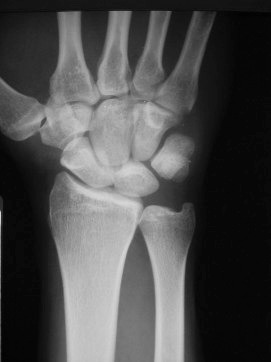

This X-ray shows the normal orientation of the bones in the wrist.

This X-ray shows the orientation of the bones in the wrist when there is a severe scapholunate ligament injury.  The scapholunate ligament is completely disrupted and allows the scaphoid and lunate to completely separate from one another.  Often the findings are not this obvious and more sophisticated  imaging studies may be necessary to make the diagnosis.